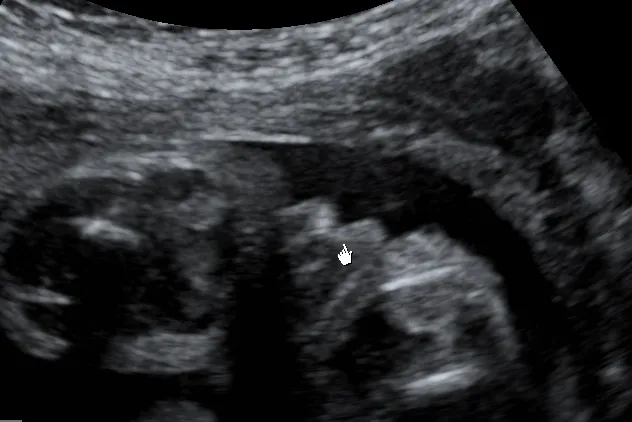

Jeśli chodzi o ultrasonograficzną ocenę płci, USG połówkowe, wykonywane między 18. a 22. tygodniem ciąży, to absolutny "złoty standard". W tym okresie narządy płciowe są już na tyle rozwinięte i wyraźne, że ich identyfikacja jest znacznie łatwiejsza i pewniejsza. Skuteczność oceny płci w tym czasie wynosi ponad 98-99%, co czyni ją najbardziej wiarygodną metodą wizualną. Aby jednak ocena była trafna, muszą być spełnione pewne warunki:

- Korzystne ułożenie płodu: Dziecko powinno być ułożone w taki sposób, aby narządy płciowe były dobrze widoczne.

- Odpowiednia ilość wód płodowych: Wystarczająca ilość płynu owodniowego zapewnia lepszą wizualizację.

- Brak przeszkód: Pępowina, rączka czy nóżka nie powinny zasłaniać obszaru narządów płciowych.

- Doświadczenie lekarza: Umiejętności i wprawa ultrasonografisty są kluczowe.

- Jakość sprzętu: Nowoczesny aparat USG z dobrą rozdzielczością znacząco ułatwia diagnostykę.